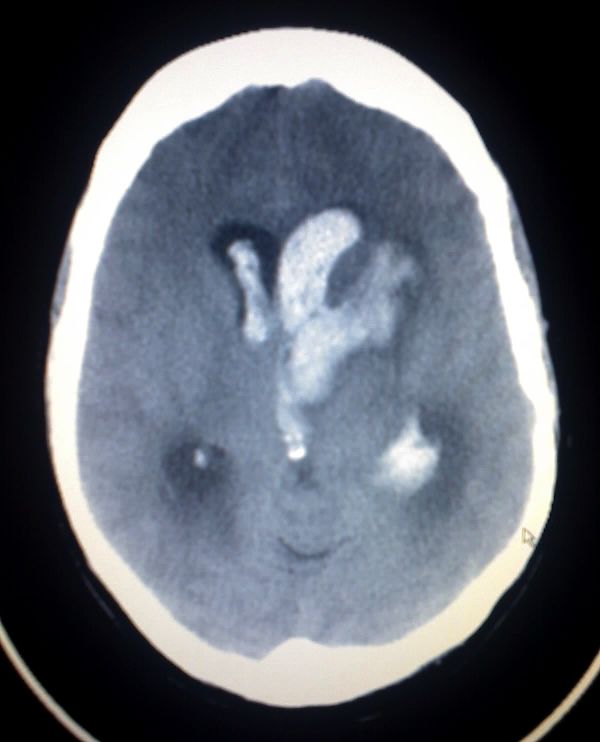

Example 4

Diagnosis

Intracerebral Haemorrhage

Example 5

Intraventricular Haemorrhage